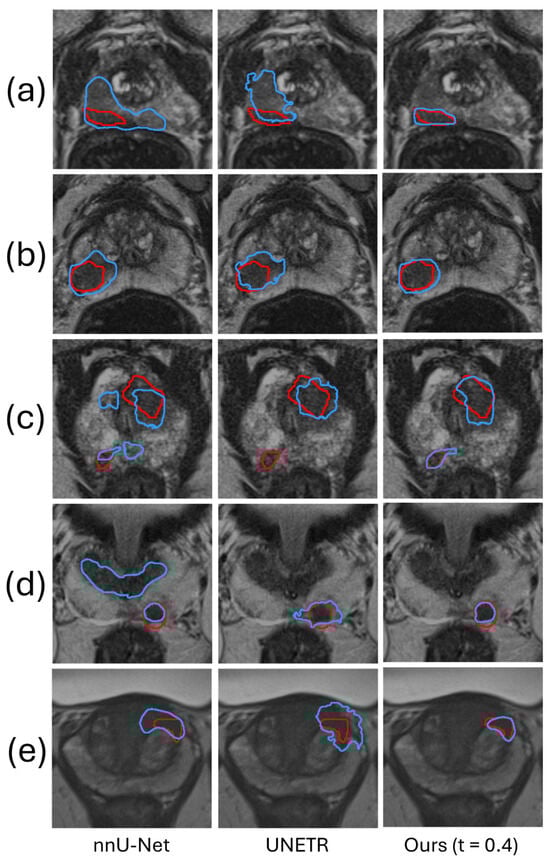

5.1.3. Lesion-Level Analysis